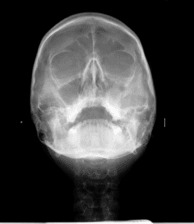

Телерентгенография (CEPH)

Телерентгенографията (CEPH) е профилна снимка на черепа. Обикновено се прави на деца за нуждите на ортодонтията. По нея лекарите измерват и анализират захапката, планират необходимите корекции и проследяват развитието на челюстите и зъбите.